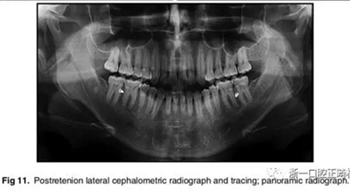

影像學(xué):全景片示:牙根平行度可。頭顱側(cè)位片及疊加圖示:下頜骨發(fā)生逆時(shí)針旋轉(zhuǎn),面部輪廓改善;上切牙轉(zhuǎn)矩正常,下切牙輕微舌傾;唇突度減小,鼻唇角增大。